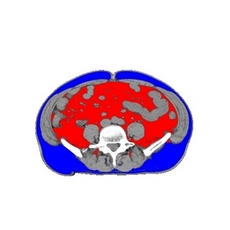

【右】当院でCTスキャンにより撮影した内臓脂肪画像。

栄養指導の際にも利用しています。